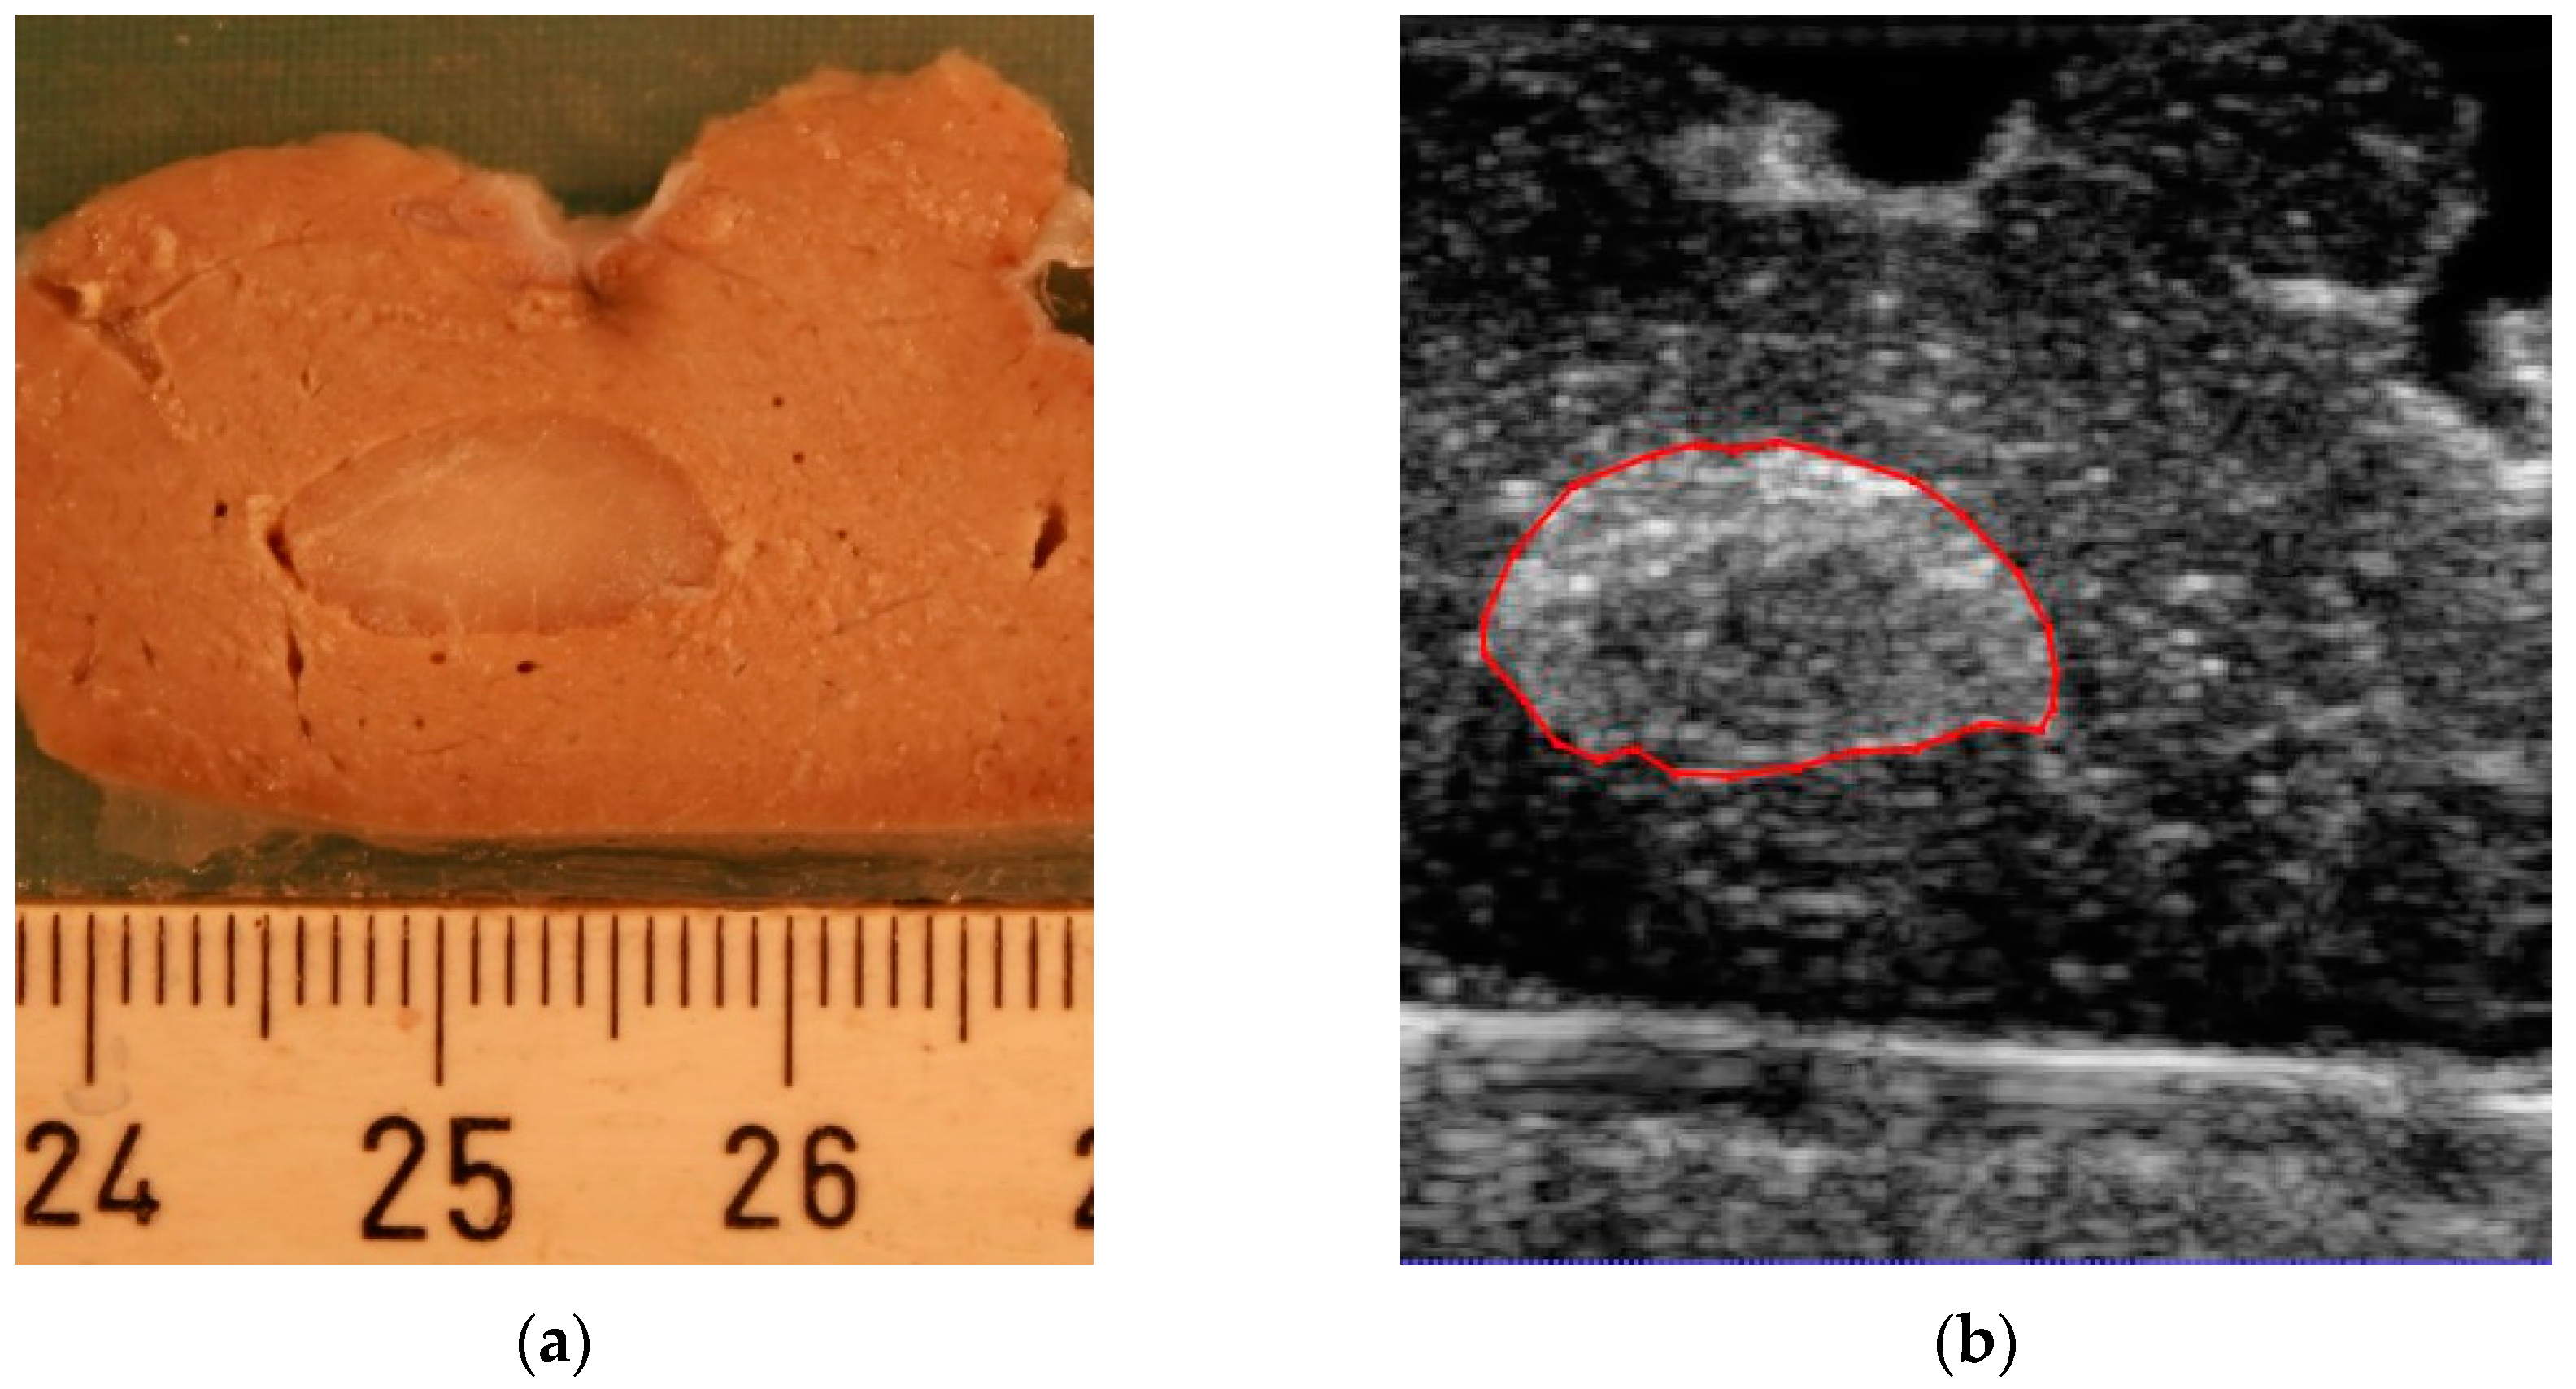

By the slicing technique described above, the model was sliced into 18 parallel 2 mm thick sections. A total of 11 of the slices included the tumor. When slicing the model, two of the slices were damaged, so we did not include them in the experiment. An example of the correlation between slices for gross pathology assessment and the corresponding 3D ultrasound and CT is presented in Figure 3. Figure 3a shows the digital image from a 2 mm thick slice. The corresponding planes from the 3D ultrasound volume and CT are presented in Figure 3b,c, respectively. Figure 3d shows the segmentation result in which two different labels are allocated to the tumor and surrounding healthy tissue region. A 3D image of the segmentation result is presented in Figure 3e.

Figure 3.

An example of the correlation between slices for gross pathology assessment and corresponding imaging. (a) Specimen slice, (b) corresponding slice on 3D ultrasound image, (c) corresponding slice on CT image, (d) corresponding slice on segmentation, and (e) 3D segmentation of the animal model.

In this experimental study, we found that 3D ultrasound is a feasible and accurate imaging method to assess the tumor volume in an animal specimen. The method is comparable to CT. The results were correlated to the gross pathological findings, which were considered the gold standard. An almost consistent standard deviation was observed in the results of 3D ultrasound (Figure 4a), with a higher variation present in the results obtained by CT (Figure 4b). These results suggest higher predictability of the accuracy of the results obtained from 3D ultrasound compared to CT. In addition, the standard deviation of the 3D ultrasound technique covered most of the data from gross pathology, while this was not the case in CT. Together, this points to the possibility of obtaining results closer to the pathological assessment by the ultrasound method compared to CT. Another advantage was the higher resolution of the ultrasound in the imaging of superficial soft tissue compared to CT, as can be seen in Figure 3b,c. The higher resolution in ultrasound volume led to a higher differentiation between the tumor and healthy tissue. Therefore, it was easier to delineate the tumor borders.